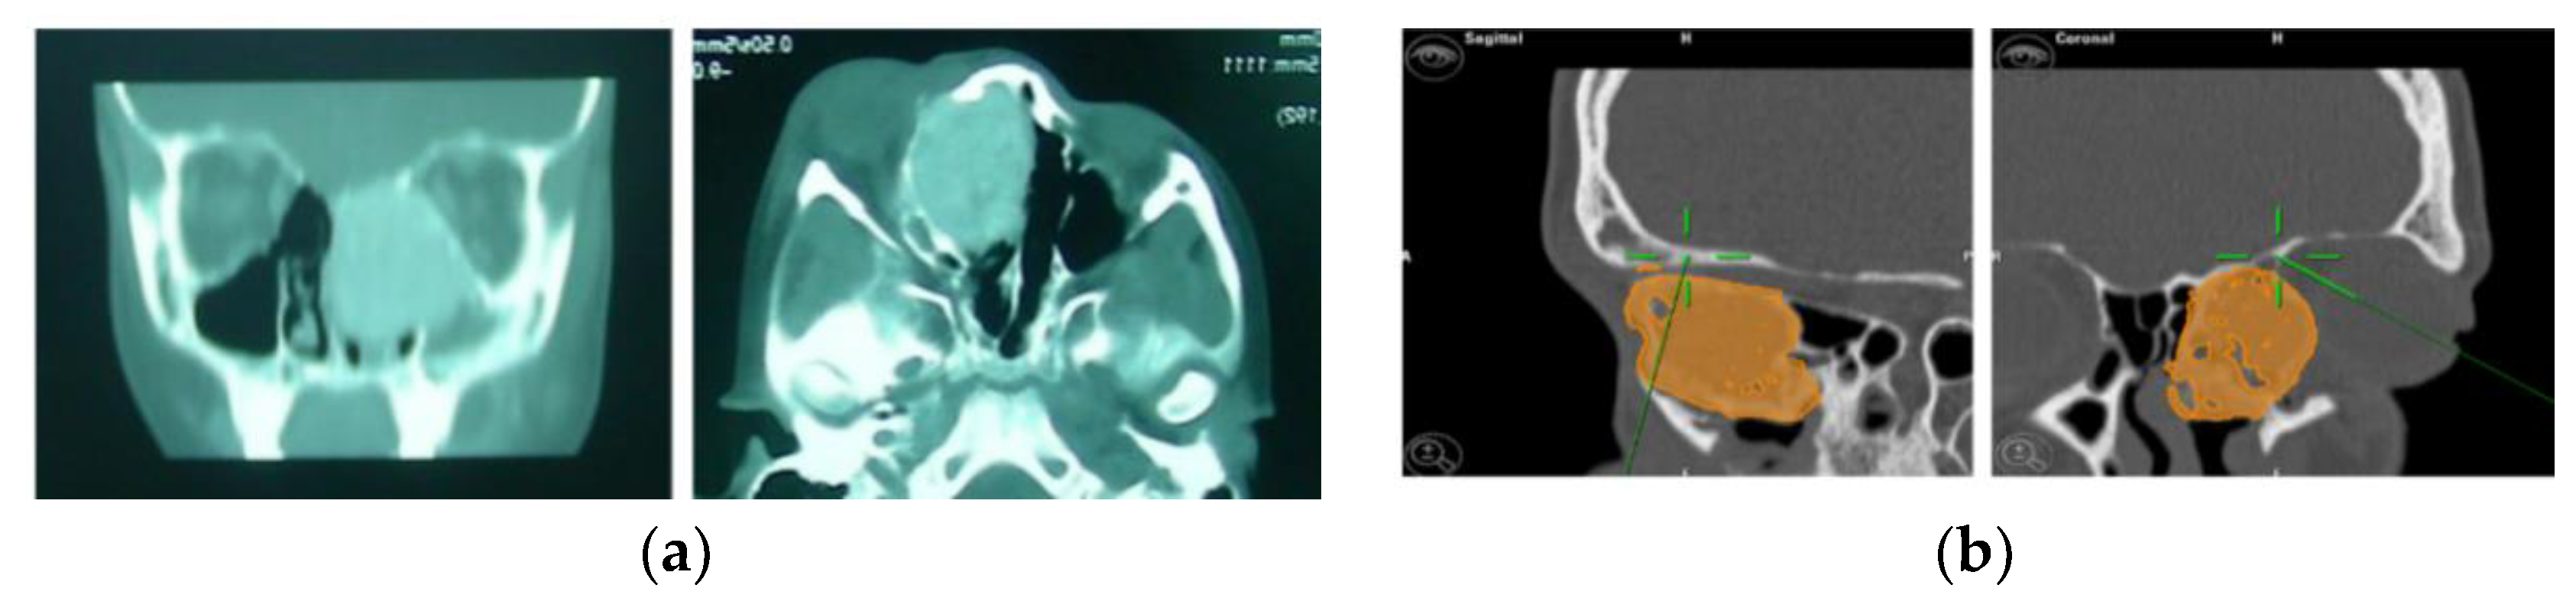

4. CASE 2: Nose-Orbital-Ethmoidal-Frontal Ossifying Fibroma Resection

A 20-year-old female patient came to us due to the persistence of a neoplasm in the left naso-ethmoid-frontal-orbital region. At the age of 7, she reported the development of a left nasal neoplasm, with a histological biopsy confirming a diagnosis of fibrous dysplasia. She had previously undergone multiple surgical procedures across different surgical centres to remove the neoplasm. A re-evaluation of the histological slides was conducted, which yielded a diagnosis consistent with ossifying fibroma.

A preoperative CT scan was performed, and the resection margins of the neoplasm were prototyped with the assistance of the iPlan 3.0 software by Brainlab (Figure 5). The operation was performed under general anaesthesia, utilising the navigation system. The DRF system was positioned in the right parietal region, ensuring a navigation accuracy of <0.5 mm. The surgical intervention was performed with a left transconjunctival retrocaruncular approach. The resection was performed using a “piecemeal” technique with a tracked chisel and a mini-saw, while the resection margins were monitored under the guidance of surgical navigation (Figure 6). The instruments were registered by anchoring the three reflecting spheres of the tracking tool to both its handpiece and the edge of the chisel, while the marked tip of the mini-saw served as a reference for navigation. The reconstruction of the medial wall and the left orbit floor was made with a pre-moulded titanium mesh (Figure 7).

Figure 5.

(a) Preoperative CT scan showing the tumour. (b) Virtual planning of resection margins.